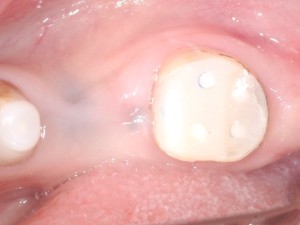

コンポジットレジンを築盛しました。(下写真)

このように歯髄腔を避けてホール(穴)を形成して土台を製作す方法も行うことができます。(※歯の幅が薄い場合はできません。)